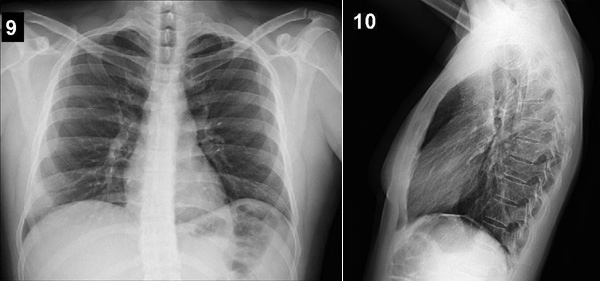

Placa 9 y placa 10

Localice en estas placas los siguientes elementos morfológicos:

- apófisis espinosas

- escápulas

- senos costofrénicos laterales

- senos costofrénicos posteriores

- burbuja de aire del estómago

- bronquios principales

- traquea

- hilios

- cisura oblicua

- cisura horizontal

- botón aórtico

- arteria pulmonar izquierda

- arteria pulmonar derecha

- lobulo medio

- lobulos superiores